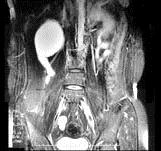

问题 女,31岁,右侧腰部胀痛不适,MRI检查如图所示,下列说法正确的是 ( )

选项 A、左肾输尿管未见异常 B、考虑为右侧输尿管囊肿 C、右侧输尿管粗细不均并迂曲扩张 D、右侧输尿管下段呈囊样扩张 E、右肾重度积水

答案 ABCDE